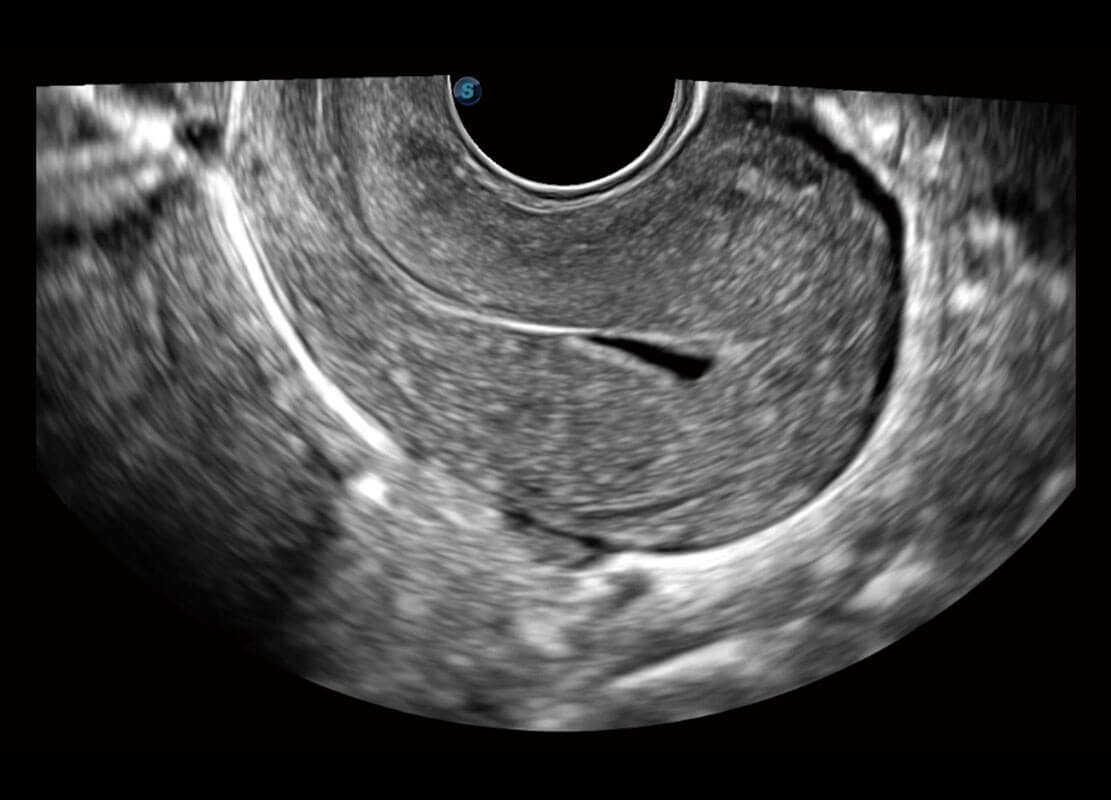

P60优异的图像质量搭载专科探头,在妇科基础疾病的诊断、卵泡生长的监测、输卵管通畅情况的判别等方面为您提供生殖应用方案。

腔内妇科-卵巢

腔内三维-宫内节育器